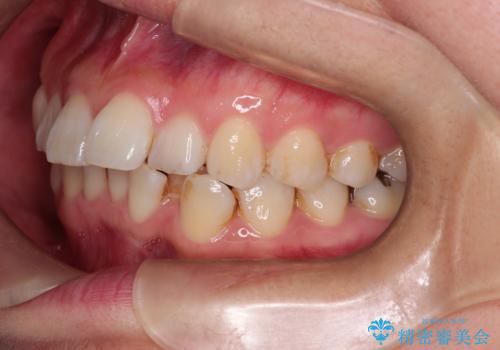

- 「歯のガタつきが気になる」「前歯の真ん中がずれている」との主訴で来院されました。診察の結果、上下の歯列に中等度の叢生(凸凹)があり、特に前歯の位置のずれ(正中の偏位)が目立つ状態でした。見た目だけでなく、かみ合わせにも影響を与える可能性があるため、全体的なバランスの改善が必要と診断しました。

治療はインビザラインを使用し、1~2週間ごとに新しいマウスピースに交換しながら段階的に歯を移動させていきました。特に上下の正中が揃うよう、奥歯や前歯の位置関係に注意を払いながら細かく設計を調整。途中の確認でも、左右のバランスが取れてきたことをご本人も実感されていました。

治療期間は約1年半で、ガタついていた歯列はきれいに整い、上下の前歯の真ん中もぴったりと揃えることができました。透明なマウスピースのため周囲に気づかれず治療が進み、快適に続けられたとの感想もいただいています。